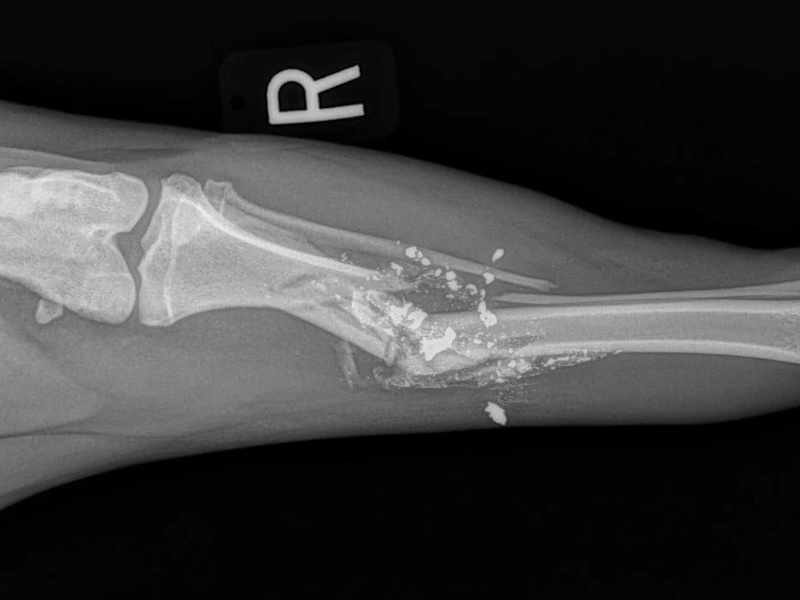

Fore Limb (Humerus, Radius/Ulnar, Metacarpus)